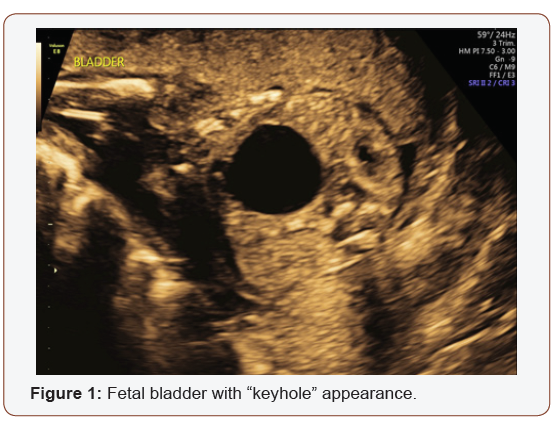

Fetal anatomy survey performed at 20 weeks gestation revealed multiple fetal anomalies, including bilateral cystic dilation of the pelvic and calyceal spaces, bilateral hydronephrosis, an enlarged urinary bladder, and oligohydramnios. Several sonographic images suggested a dilated posterior urethra, demonstrated by the pathognomonic “keyhole appearance”. PUV was suspected at this time and close follow-up was recommended. The patient was evaluated again at 22 weeks gestation, and a targeted fetal ultrasound revealed worsening oligohydramnios with persistent distention of the urinary system. These findings confirmed the suspicion of posterior urethral valve disorder.

The patient was counseled on the findings and expectations of this anomaly during the anatomy scan and genetic testing was offered. Amniocentesis showed elevated AFP (23.1 mcg/mL) and chromosomal analysis revealed a 46XY fetus. Additionally, the chromosomal micro assay exhibited a fetal chromosomal abnormality: arr [hg19] 16q24.2 (88, 059, 561-88, 647, 325) x 3. Approximately 588 kb interstitial gain of 16q24.2 was detected in this male fetus. This duplication included a segment of the BANP gene (OMIM: 611564), complete copies of the genes ZNF469 (612078), ZFPM1 (601950) and MIR5189, plus a segment of the ZC3H18 gene (not annotated in OMIM) (Figures 1-5).